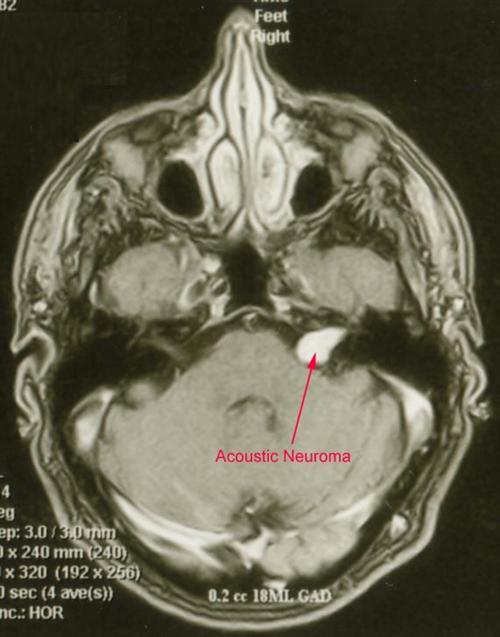

听神经鞘瘤是什么原因

第一:发病原因   神经鞘瘤起源于施万细胞。虽然有一些关于神经瘤病因的推测,但直到现在还没有完全找到真正的诱发因素。目前最倾向的原因是:肿瘤抑制基因缺失。

第二:发病机制   肿瘤具有完整的包膜,切面可呈淡红、灰白或黄色。有时可见由变性而形成的囊肿,内含血性液体。镜下见瘤实质主要由神经鞘细胞构成,偶见成熟神经节细胞和神经干参与。